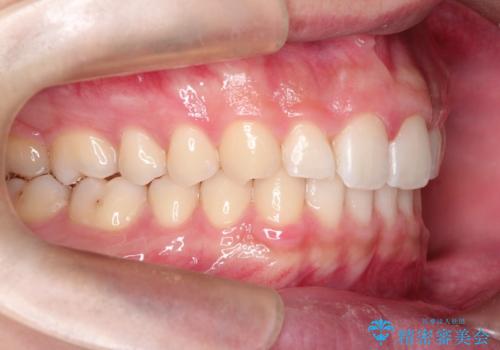

見た目、噛み合わせ及び、治療期間や施術内容に大変ご満足いただきました。

- 治療期間

- 2年5ヶ月